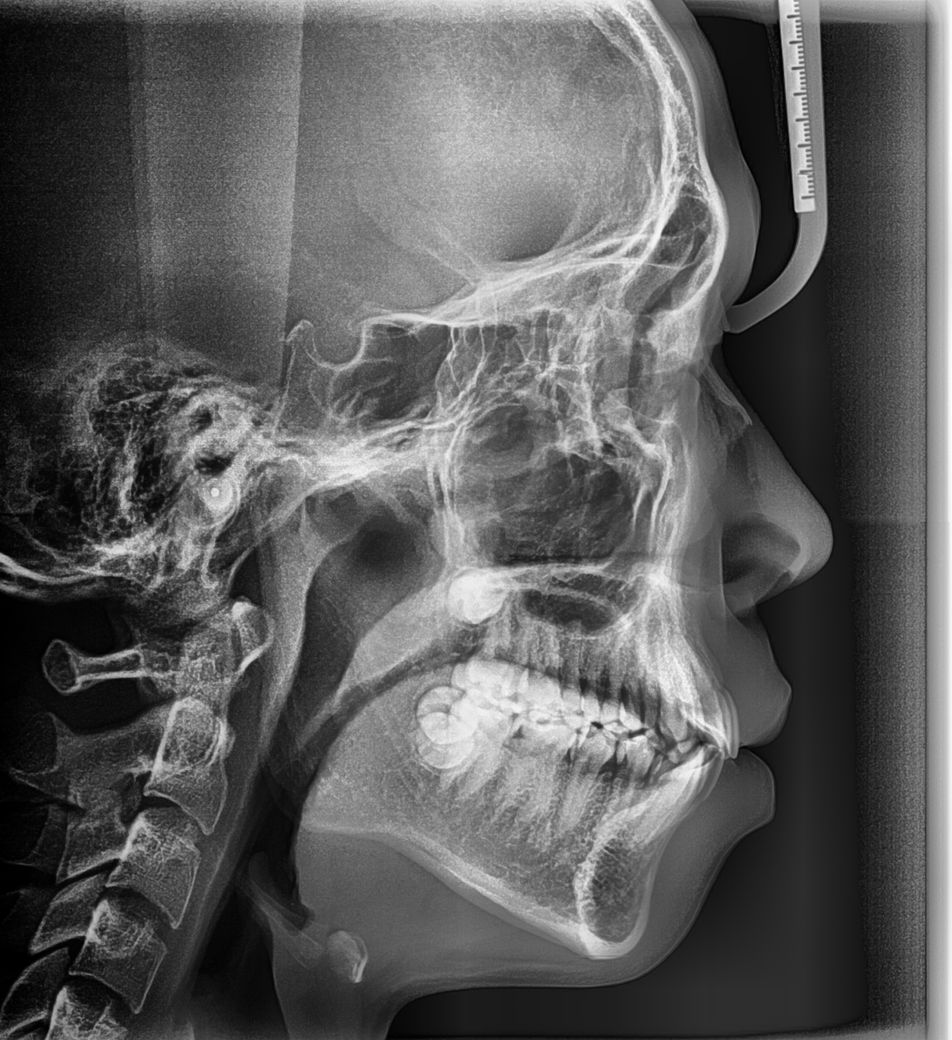

위3개는 교정전 사진이에요

• 1번 째 사진